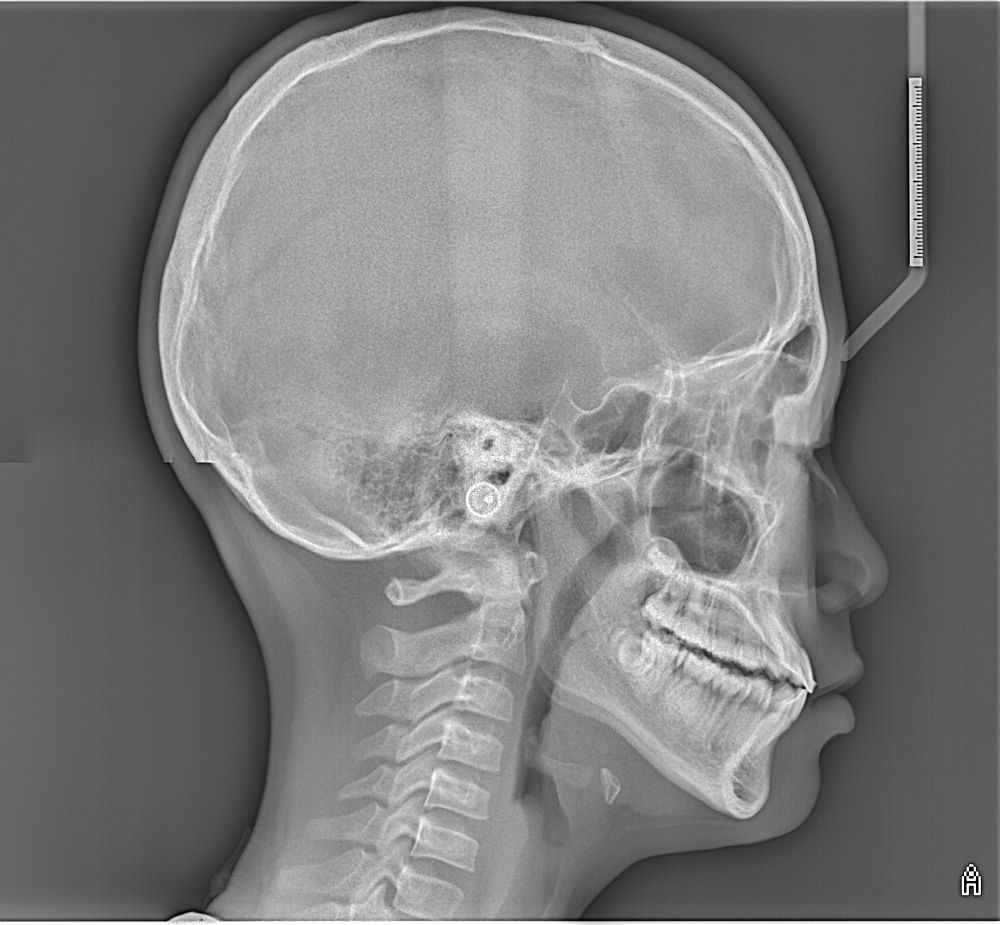

A real case: A girl that came at 17

Actual patient results. Individual outcomes may vary.

Before

After

We can align her teeth but we can’t make her bone grow unless we do jaw surgery.